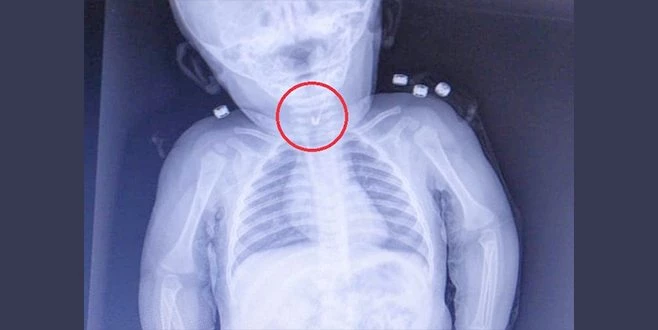

Tekirdağ?da 7 aylık bebeğin yemek borusundan ucu açık çengelli iğne çıktı.

Tekirdağ?da 7 aylık bir bebek, yemek borusuna çengelli iğine kaçması sonucu Tekirdağ Devlet Hastanesi`ne sevk edildi.

7 aylık erkek bebeğin yutup yemek borusuna takılan açık çengelli iğne Tekirdağ Devlet Hastanesi`nde yapılan girişim ile başarıyla alındı. Gastroenterolojik Cerrahi Uzmanı Dr. İhsan Gündüz ile Anestezi Uzmanı Dr. İbrahim Çetin`in yaptığı operasyon sonucu bebek sağlığına kavuştu.